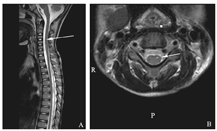

诊疗经过:入院后神经内科会诊意见:诊断急性麻痹综合征、呼吸衰竭、肺炎。予气管切开、机械通气辅助呼吸,甲强龙2 mg/(kg·d)静点抗炎,营养神经等治疗。复查脑脊液常规及生化正常。脑脊液免疫学指标阴性。细菌学结果均阴性。血清及脑脊液分子生物学提示EB病毒、肠道病毒、疱疹病毒等均阴性。送检患儿咽拭子及便标本至北京市疾病预防控制中心,咽拭子标本提示肠道病毒-D68(EV-D68)病毒核酸弱阳性,便标本阴性。复查头颅增强核磁未见异常,脊柱增强核磁示:颈2-颈6脊髓前角条状T2高信号影(图1)。肌电图示神经源性损害。入院10 d激素逐渐减停,并予机械通气撤机锻炼。病情恢复缓慢,住院4周后,患儿可间断脱机,右上肢肌力Ⅱ-级,右手手指可抓握,左上肢肌力0级,双下肢肌力Ⅴ级。联系外院行康复治疗。出院诊断:急性脑脊髓炎、呼吸衰竭、肺炎。追踪患儿,已逐渐脱离呼吸机,继续康复中。

A:矢状位T2WI,颈2-颈6信号增强(箭头);B:横向T2WI,脊髓前角条状高信号,左侧明显(箭头)。